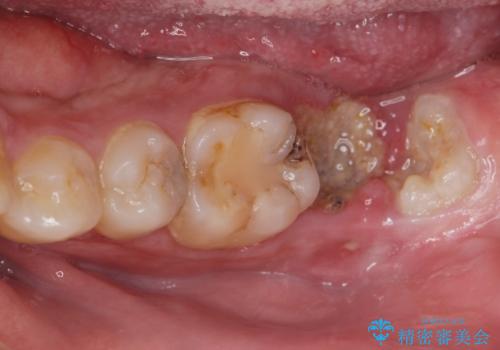

まず徹底的に虫歯を取り除き、保存が出来ない部位は抜歯(親知らずを含む)を行い、根管治療が必要な部位は精密根管治療を行いました。

また、虫歯が歯肉の中まである場合はAPF(歯肉弁根尖側移動術)も行なっています。